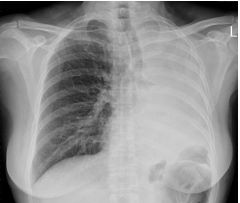

3. 66歲婦人因咳血和呼吸困難求診,胸部X光如圖,請問下列何者對診斷最有助益? (A) 抽動脈血氣體分析 (B) 做胸腔穿刺抽水檢查 (C) 做痰檢查細菌與癌細胞 (D) 做支氣管鏡檢查 (E) 做核醫肺部掃瞄